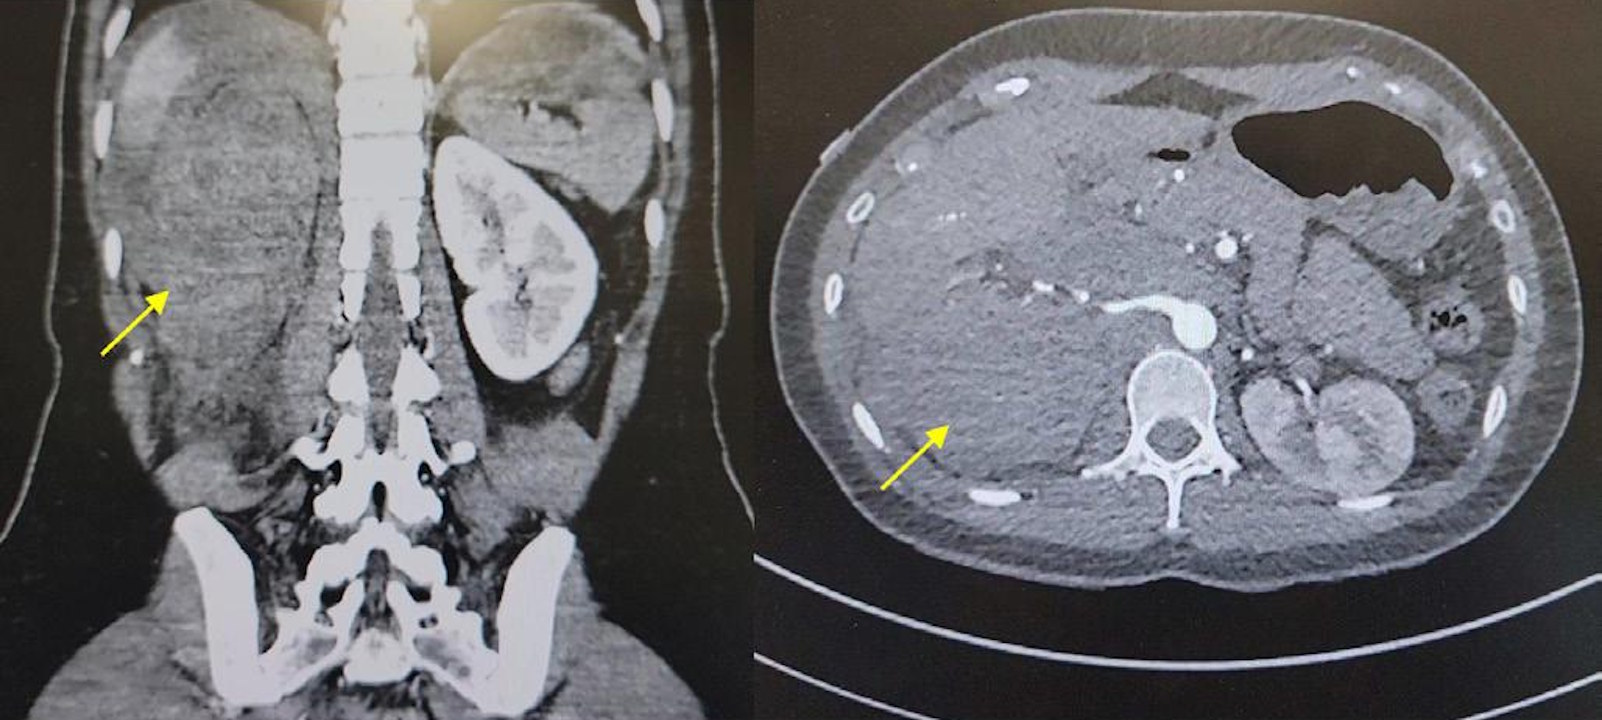

Кровотеча в черевній порожнині (позначена жовтою стрілочкою) на знімках комп'ютерної томографії пацієнтки. Rampersad et al. / BMJ Case Reports, 2025

Оскільки у пацієнтки з’явилися труднощі з сечовипусканням і знизився рівень гемоглобіну в крові, лікарі запідозрили кровотечу в черевній порожнині. Їй провели комп’ютерну томографію, яка підтвердила пошкодження внутрішньої частини правої нирки, зокрема її судин. Після обстеження в жінки різко знизився тиск, тож їй швидко зробили переливання крові та ввели ліки для сповільнення кровотечі. Також їй провели емболізацію ниркової артерії — ввели в неї штучний тромб, щоб зупинити кровотечу. За місяць після виписки жінка не мала жодних ускладнень.